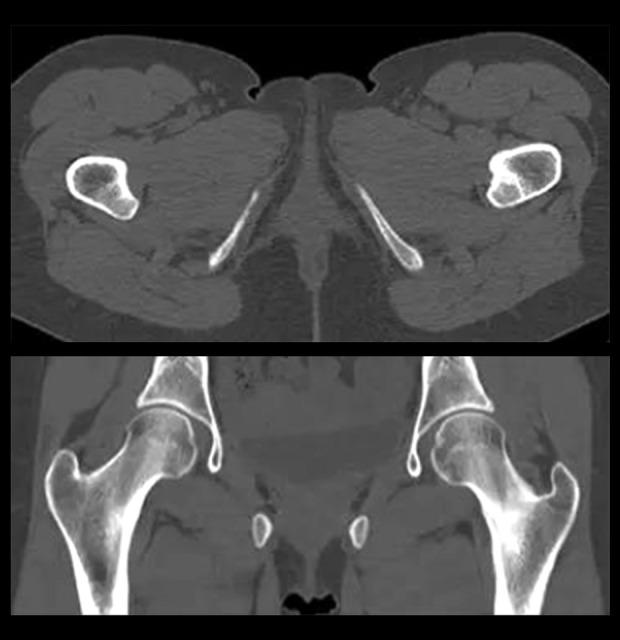

BACKGROUND The purpose of this research was to study and analyze the diagnostic value of magnetic resonance (MR) combined with computed tomography (CT) in patients with stress injury of the femoral neck. MATERIAL AND METHODS The 58 patients with stress injury of the femoral neck who were treated in our hospital from July 2017 until July 2019 were selected as subjects on the basis of clinical pathology and surgery, MR and CT examination, and related imaging data retrospectively analyzed. We observed all patients using different diagnostic methods to determine the value of diagnosis and treatment of disease. RESULTS The patients selected for this study were confirmed by clinicopathology and surgery; the positive rate of CT diagnosis was 65.5%, the positive rate of MR diagnosis was 74.1%, and the positive rate of combined diagnosis was 91.4%. Through statistical analysis, CT and MR showed no significant difference in the detection of stress lesions in different femoral necks, indicating no statistical significance (P>0.05). However, the amount of stress lesions detected in the combined diagnosis was higher than that in the two separate detection methods, with statistically significant difference (P<0.05). The grading of stress lesions in all patients examined through MR showed that there was no proportion of grade 0, whereas grades 3-4 were the highest, accounting for 20.7% and 32.8% respectively. In CT scanning of all patients, fracture lines were observed in 35 patients, of which 25 were transparent lines and 10 were strip dense shadows; Periosteal reaction was observed in 34 patients, of whom umbilical concave was observed in 18 patients. Osteoporosis was observed in 30 patients, and the lesion showed a zone of reduced density in the cortical bone, with a stripelike shape and unclear boundary. The density tended to increase in the cavum medullare of 32 patients, with porosis being visible. Compared with CT diagnosis, the accuracy, sensitivity, and specificity of MR detection were not significantly different (P>0.05). The accuracy, sensitivity, and specificity of the combined detection were higher than that of CT and MR detection alone, with statistically significant differences between groups (P<0.05). CONCLUSIONS The application of MR combined with CT in early clinical diagnosis and treatment of femoral neck stress injury will improve the diagnosis rate; the imaging signal is obvious, which is helpful to further evaluate the severity of disease.